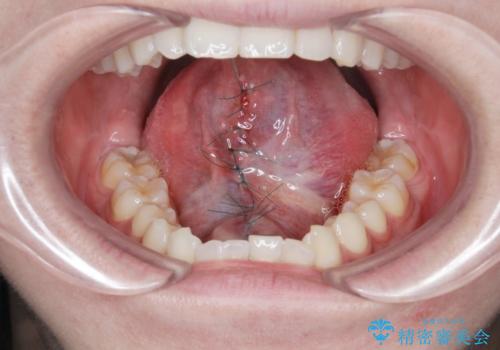

滑舌の改善 舌小帯の形成術

小手術は5〜10分程度で終了します。

- 外科手術のため、術後に出血、痛みや腫れ、違和感を伴います